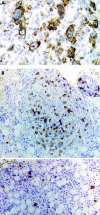

Unexpected finding on staging bone marrow aspirate for Hodgkin's lymphoma